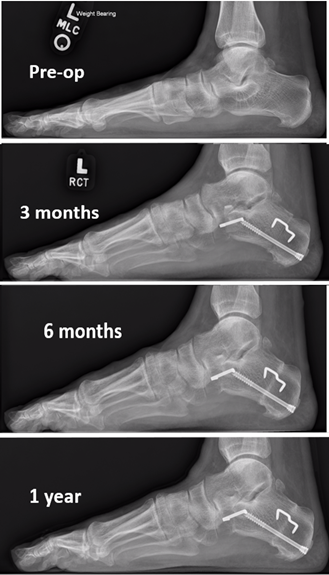

The Cotton Osteotomy In Flexible Flatfoot Correction

The Cotton Osteotomy in Flexible Flatfoot Correction www.hmpgloballearningnetwork.com